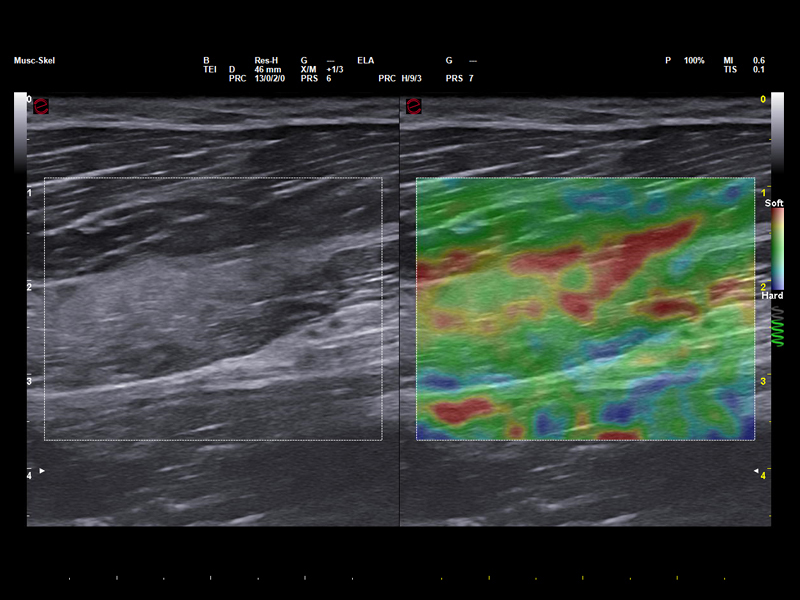

Advanced tissue imaging for athletes

Elastosonography is a highly valuable tool in the field of sports medicine, offering key insights into the mechanical properties of muscles, tendons, and ligaments, thus supporting injury diagnosis, recovery monitoring, and return-to-play decisions. ElaXto, Esaote’s real-time strain elastography, provides real-time visual feedback through color-coded stiffness maps, which are ideal for the assessment of overuse injuries, while QElaXto 2D, based on shear-wave technology, delivers quantitative elasticity values, which are useful for tracking tendon healing and guiding rehabilitation.